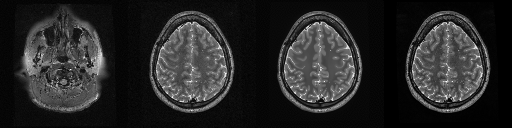

HCP T2w dataset

We utilize images from the publicly available Human Connectome Project (HCP) [51] T2-weighted (T2w) images dataset for the task of compressed sensing, which contains brain images from 47 patients. The HCP dataset includes cross-sectional images of the brain taken at different levels and angles.

Compressed sensing

We train a flow-based model from scratch on 10,000 randomly sampled images, utilizing the ncsnpp architecture [9] with minor adaptations for grayscale images. We employ compression rates , meaning . The measurement operator is given by a subsampled Fourier matrix, whose sign patterns are randomly selected. We evaluate our reconstruction algorithm’s performance on 200 randomly sampled test images.

We present the quantitative and qualitative results of compressed sensing in Tab. 1 and Fig. 4, respectively. As shown in Tab. 1, our method consistently achieves the best performance across varying compression rates . In Fig. 4, our method produces reconstructions that are more faithful to the original images, with fewer artifacts, leading to higher accuracy and clearer details.